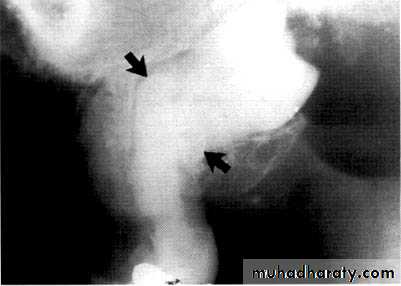

Dentin dysplasia, type I. panoramic & periapical films of the same case show the short and poorly developed roots, obliterated pulp chambers and root canals, and periapical inflammatory lesions.